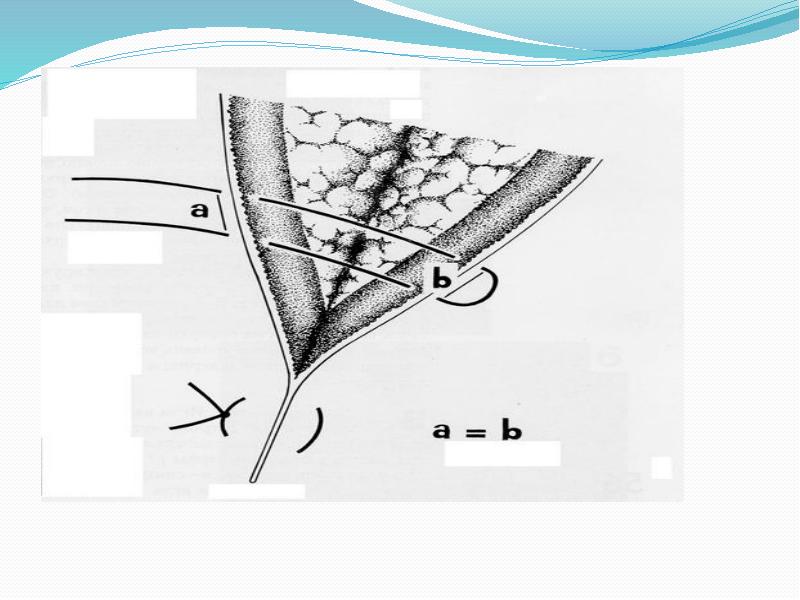

- 39. Горизонтальный матрацный шов Обычно накладывают П-образно. используется для соединения краев поверхностных